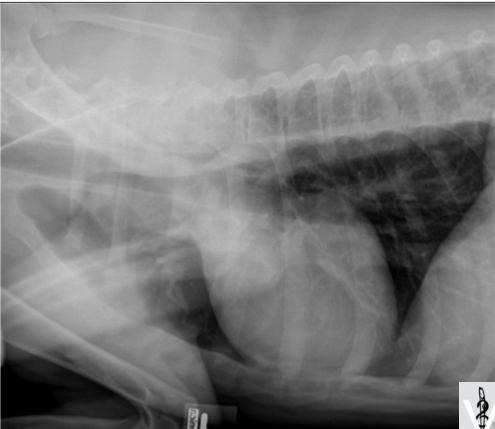

Les techniciens en sueur vous présentent la radio suivante, quelle décision prenez-vous alors?

A) faire l’interprétation de son mieux en expliquant au client nos limitations

B) donner une sédation et reprendre la radiographie plus droite

C) optez pour une contention manuelle et reprendre la radiographie plus droite

D) reprendre la radiographie en doublant le mAs

B)